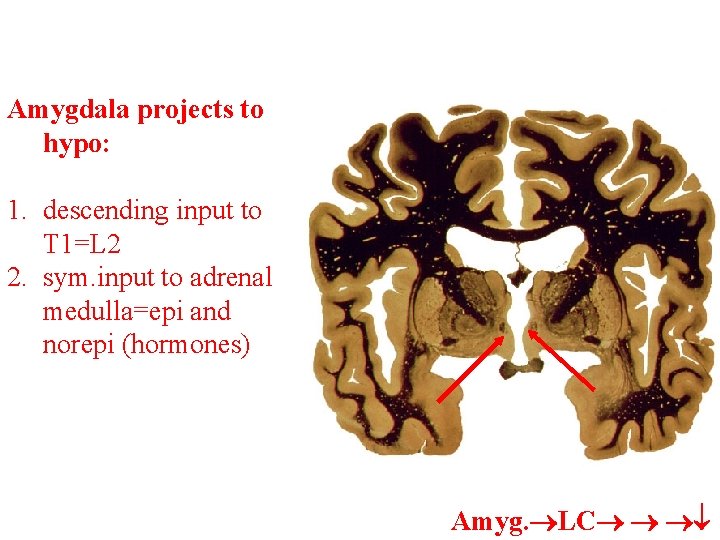

Amygdala projects to hypo: 1. descending input to T 1=L 2 2. sym. input to adrenal medulla=epi and norepi (hormones) Amyg. LC